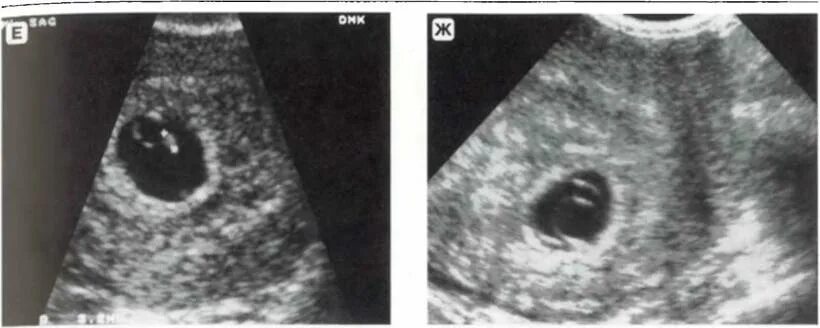

Желточный мешок увеличен